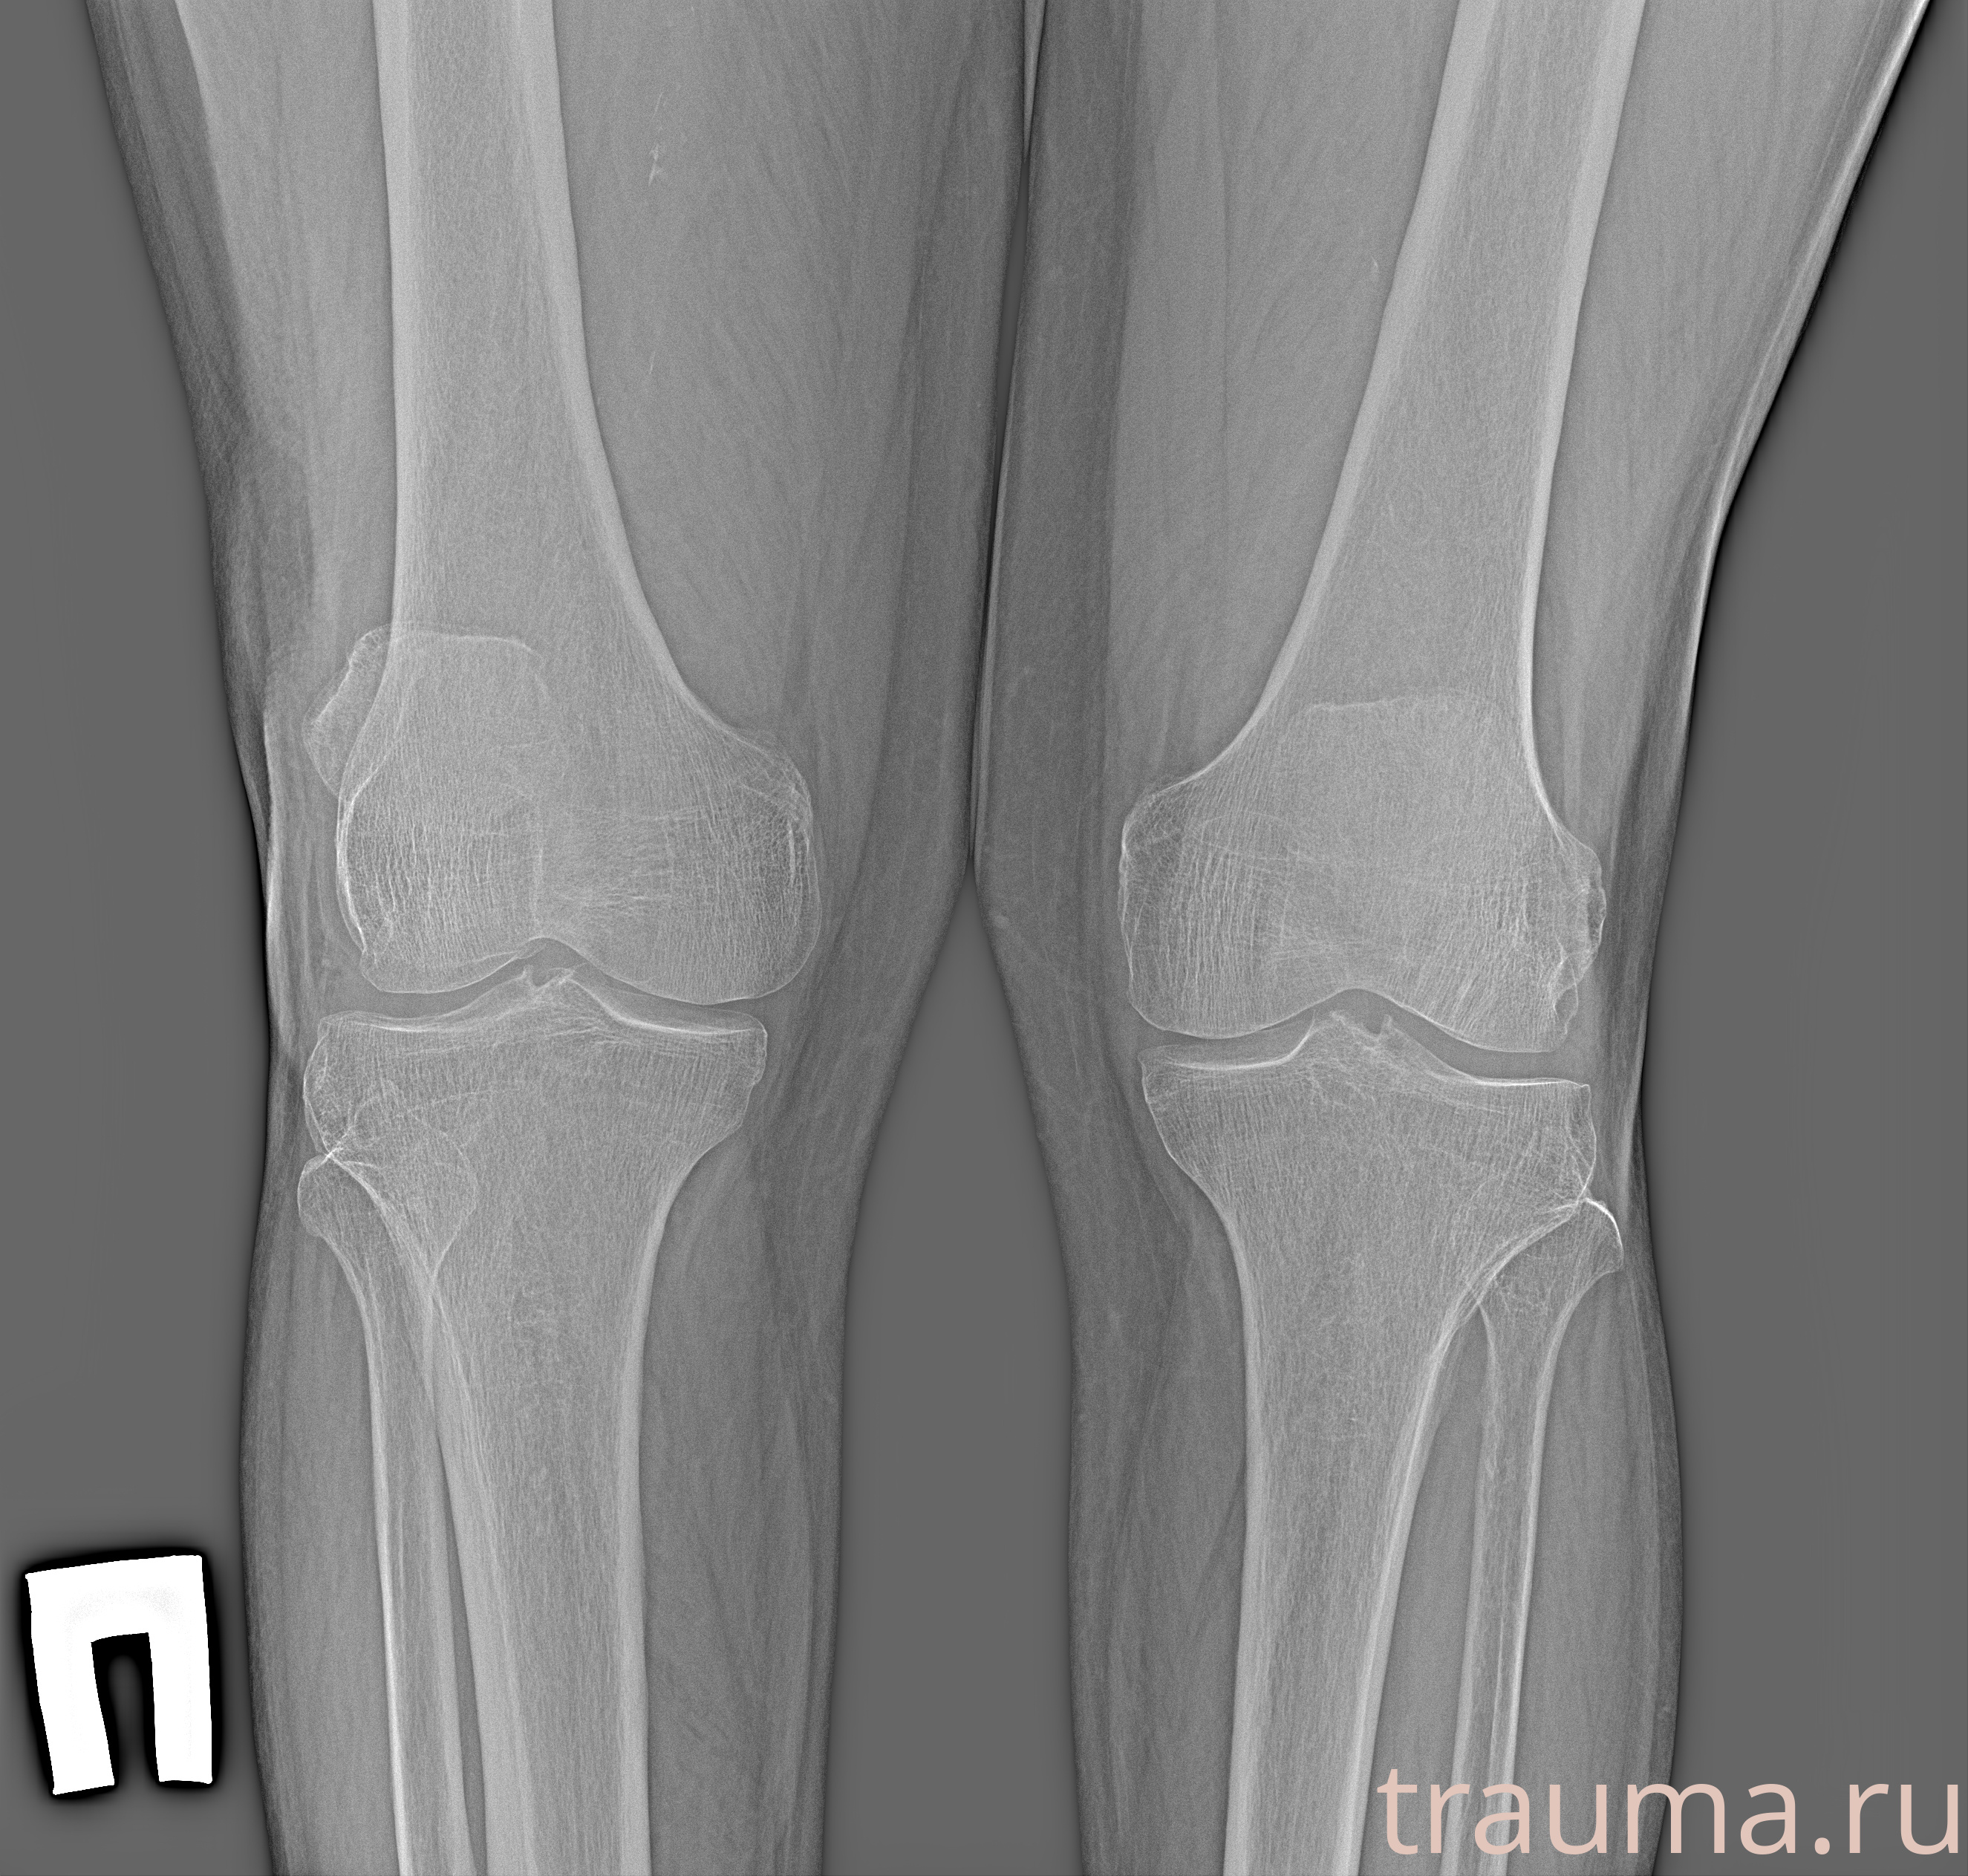

Рентгенограммы

Рентген на дому: по вашему адресу приезжает врач-рентгенолог, травматолог-ортопед с мобильным рентгеновским аппаратом, проводит диагностику травмы или заболевания, делает необходимые рентгенограммы, дает рекомендации по дальнейшему лечению. Получить качественные снимки в домашних условиях возможно благодаря уникальной методике, разработанной МосРентген Центром для института  Склифосовского